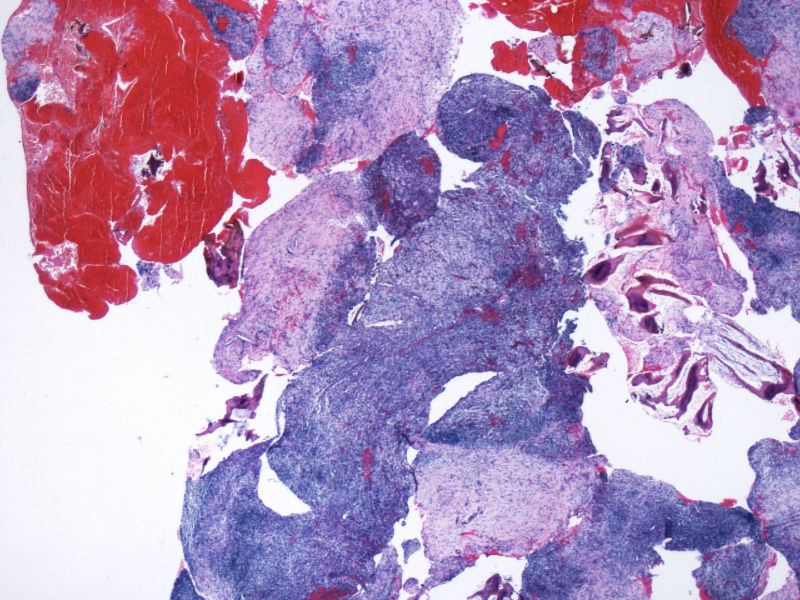

ALK阳性ALCL发病年龄,发病部位,细胞形态可以非常广泛。西方国家统计男女比例为1.5:1,主要是40岁以内,尤其是儿童青少年多发。本例46岁女性,流行病学应少见的女性发病时段;

如金老师所言原发于骨也少见,如标题所显示:“临床骶骨脓肿?”表现为骨脓肿恐怕更少,综合以上所以本例的确特殊;

形态学hallmark 细胞显示不是很清晰,大的肿瘤细胞如果在ALCL和HL之间选择可能不容易,但HL的肿瘤细胞形态学特点的范围比较狭窄,而ALCL可能具有更广泛的形态学范围,细胞大小形态以及典型hallmark cell的多少有时很难确定。如果只看HE,觉得ALCL的可能会安全一点,当然我个人经验不足,可能理解得比较肤浅。